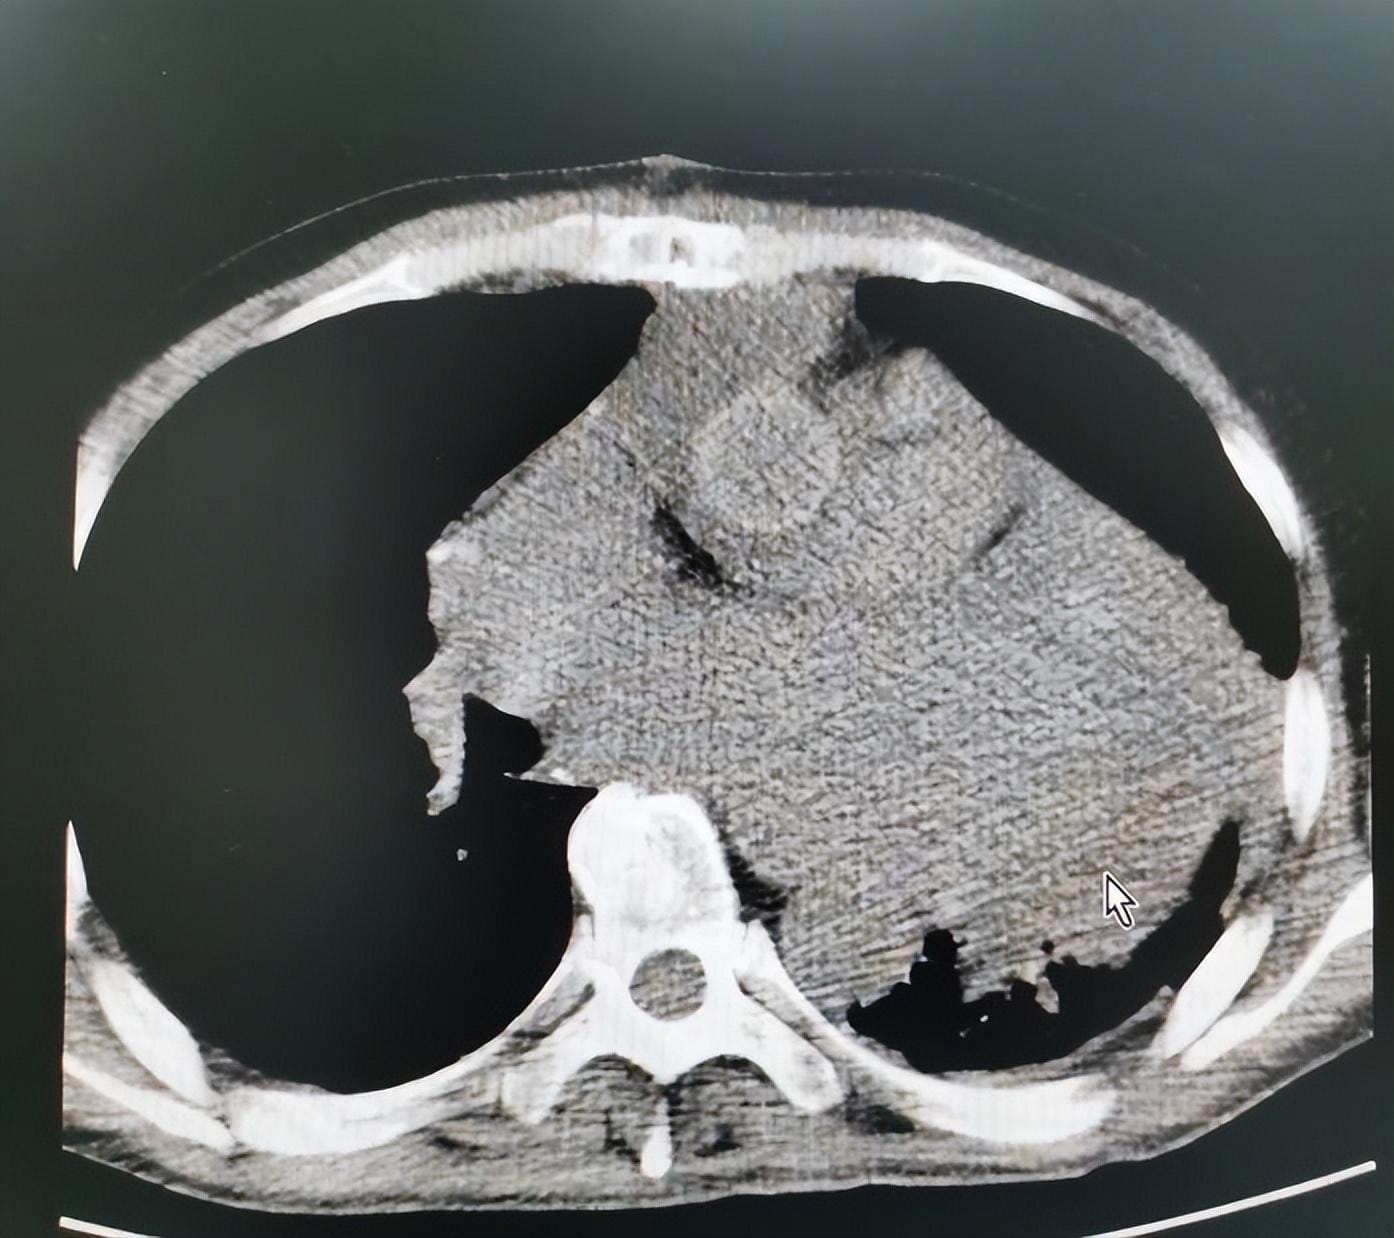

患者男性,60岁,7年前在我院行“二尖瓣置换、三尖瓣成型术”,术后恢复良好,两年前活动后出现气促、偶有头晕,现气促症状进行性加重,遂来住院治疗,以“升主动脉瘤”收住心脏大血管外科。患者高血压病多年,血压控制不详,心脏超声示左房巨大,主动脉瓣重度返流,左心室明显增大。

患者心功能较差,若不行手术治疗,病情将急剧恶化,但因患者心脏巨大,肝功能不全,术中体外循环、心脏停跳过程中可能会加重心肌缺血,致术后心功能更加受损,出现心律失常、肝肾等多器官功能衰竭的几率也会大大增加。患者此次为二次心脏手术,存在胸腔粘连,开胸难度大。考虑患者病情复杂,手术风险极高,我科联合麻醉科、心内科、ICU等多学科会诊及讨论后,最终制定了完善的手术策略,在经过术前一周的对症保守治疗后,拟在全麻体外循环下行Bentall+二尖瓣替换+三尖瓣成形术。